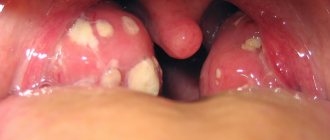

В связи с тем, что гнойные выделения из носа попадают в зев, а также необходимость длительного дыхания через рот из-за постоянной заложенности носа, синусит часто сопровождается симптомами хронического фарингита – такими как мокрота, ощущение инородного тела или боль в горле. Если есть воздействие пораженной околоносовой полости на евстахиеву трубу, то может также появиться шум в ушах, развиться глухота и другие симптомы. Из-за хронического синусита может серьезно пострадать успеваемость детей в школе, что приведет к отставанию. Хронический синусит также может быть источником заражения других органов, которые находятся в непосредственной близости к источнику воспаления.